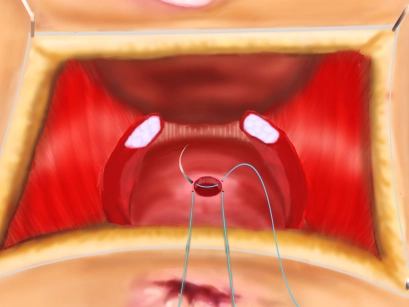

Aorta und Beckenstrombahn

Resektion eines infrarenalen Bauchaortenaneurysmas und Rohrprothesen-Interposition